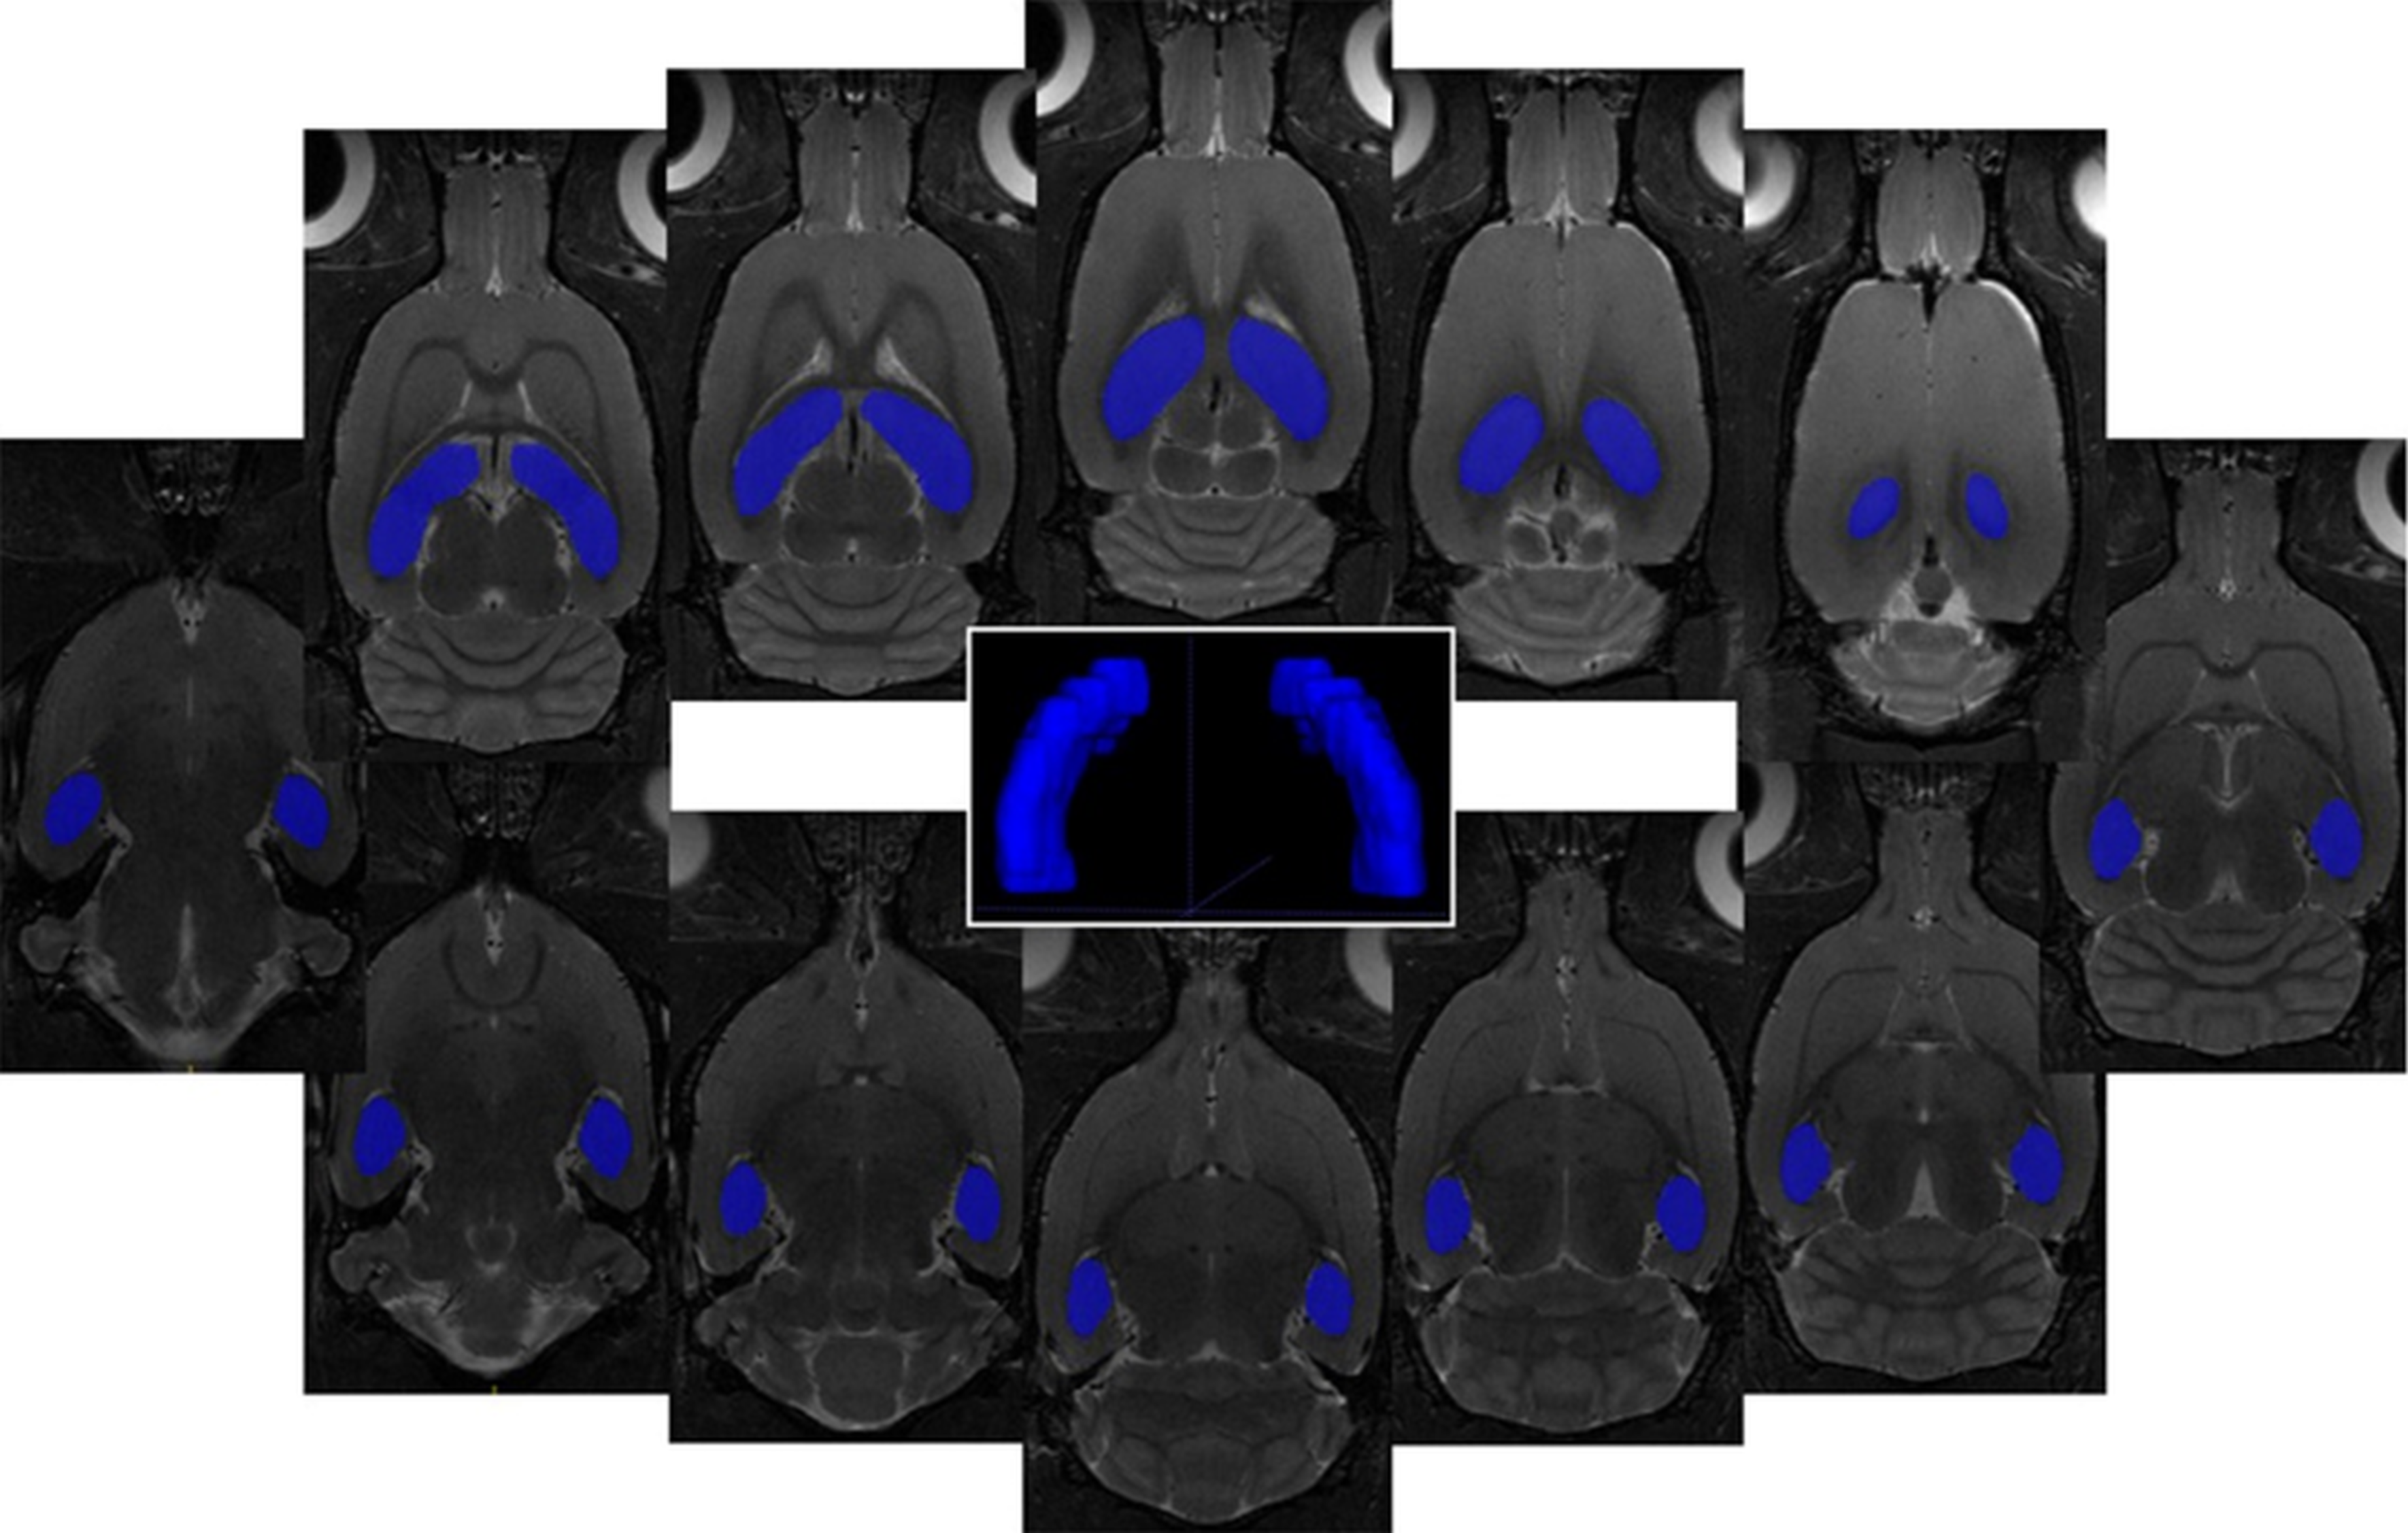

2.3. Volumetric Analysis

MRI Volumetric Analysis

| HIPPOCAMPUS | ||

|---|---|---|

| volume change mean ± SD tissue volume mean ± SD | C (volume threshold) 91.7 mm3 | MDG 10 ± 2 % |

| C 96.51 ± 4.78 mm3 | - | independent sample 2-tailed t-test |

| MDG 100.85 ± 1.82 mm3 | 0.031 | - |